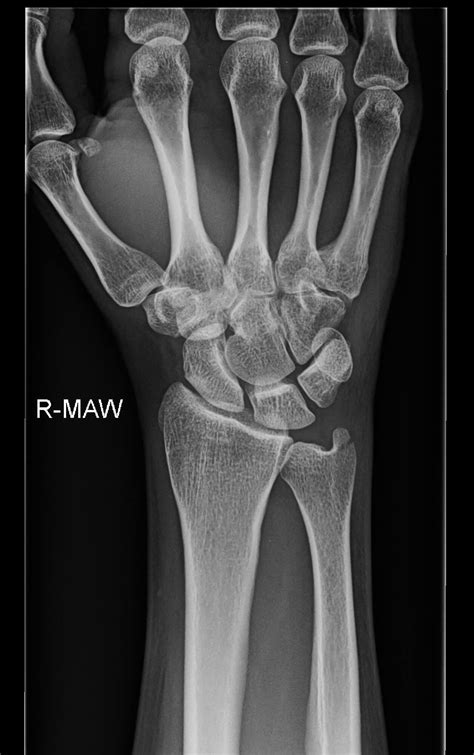

Diagnostic Approach

Diagnosing an ulnar styloid process fracture requires a comprehensive medical evaluation:

- Imaging studies including:

- X-rays